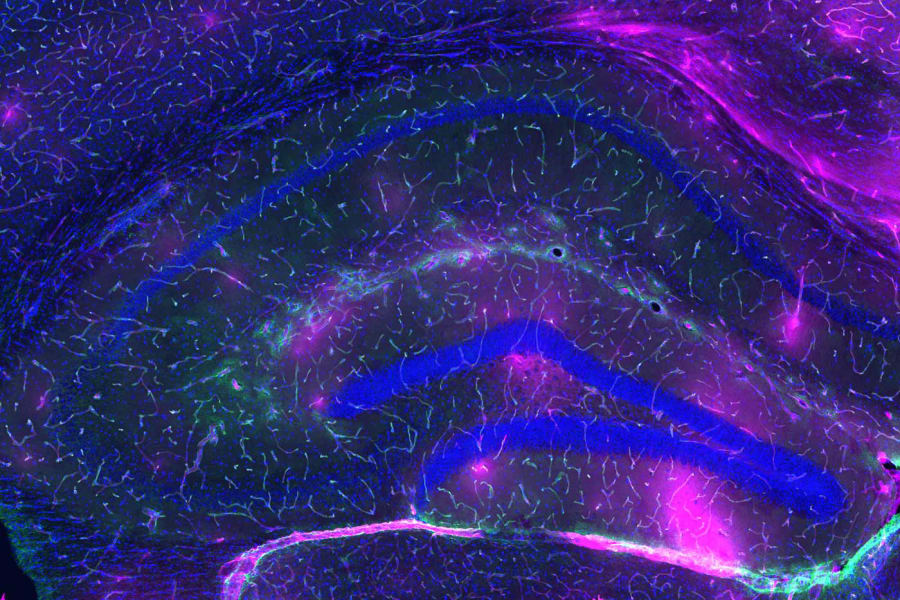

Imagen de portada